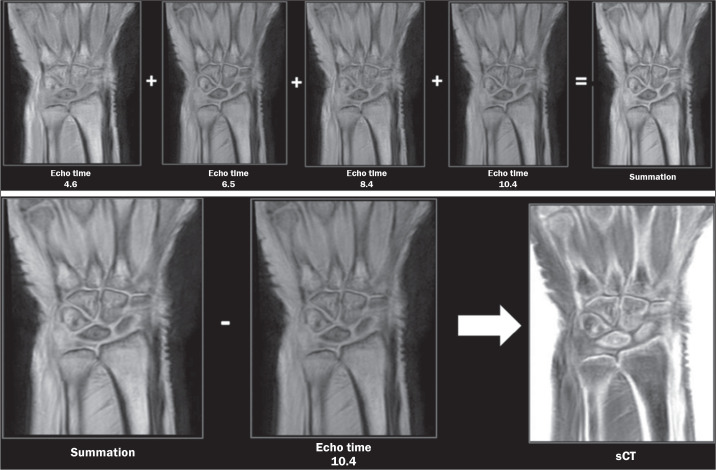

Increasing tissue contrast for bone assessment on magnetic resonance imaging has been the aim of several recent studies, and various techniques have been proposed for that purpose, including ultrashort echo time sequences, zero echo time sequences, and gradient echo sequences in various acquisition forms. In this article, we discuss the fast field echo resembling a computed tomography using restricted echo-spacing (FRACTURE) sequence, which we have started to use routinely in our practice. The FRACTURE sequences are based on the acquisition of gradient echo sequences with different echo times and specific postprocessing. Gradient echo sequences are widely available on magnetic resonance imaging scanners, which is an advantage for the use of a FRACTURE sequence. However, being more susceptible to metal artifacts, a FRACTURE sequence is of limited utility in patients with metallic implants or medical devices. The aim of this article is to illustrate the use of FRACTURE sequences in various contexts, including osteoarticular infection, inflammatory arthropathy, bone tumors, fractures, and crystal deposition diseases.